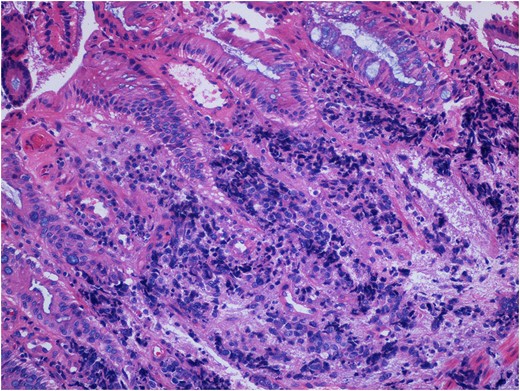

He was referred to a gastroenterologist who performed a diagnostic colonoscopy. A friable, exophytic mass was encountered 1 cm proximal to the anal verge. The pathology specimen stained positively with synaptophysin, chromogranin and TTF-1, which is consistent with small cell neuroendocrine carcinoma (Fig. 1).

Pathologic specimen consistent with small cell neuroendocrine malignancy of the rectum. This specimen stained positively for synaptophysin, chromogranin and TTF-1 (not shown). Not seen in this image is a significant necrotic contribution consistent with high-grade pathology.